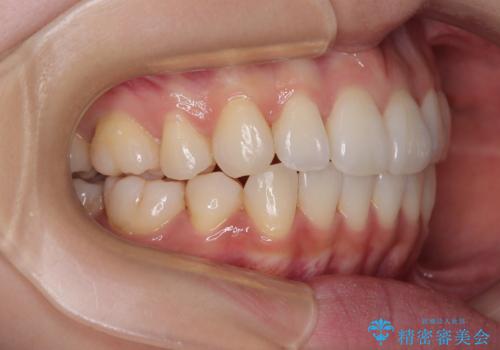

1. 抜歯矯正の軽度後戻りを解消 インビザライン矯正の治療前

2.

3. 抜歯矯正の軽度後戻りを解消 インビザライン矯正の治療後